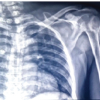

Routine blood investigations were normal. Plain radiographs of left humerus showed a permeative, destructive lesion involving the upper and middle one third with pathological fracture (Fig. 1A). Chest radiograph was normal. Magnetic resonance imaging revealed altered marrow signal intensity in the diaphysis and proximal metaphysis of left humerus. There was a large soft tissue component which was hypointense on T1, heterogeneously hyperintense on T2 and STIR images (Fig. 1B). He underwent an incisional biopsy. The histopathological (HPE) diagnosis was Ewing’s sarcoma. Immunohistochemistry showed positivity for CD99 and Bcl-2. Positron emission tomographic scans demonstrated no evidence of pulmonary metastasis. The tumour was staged as IIB according to Musculoskeletal Tumour Society Staging.

Routine blood investigations and thyroid function tests were within normal limits. Plain radiographs of right humerus showed an expansile lytic lesion causing complete destruction of the head, neck and proximal half of right humerus. (Fig. 3A) MRI revealed a large expansile, lytic lesion which was hyperintense on T2 and iso to hyperintense on T1 image. There was a breach in the cortex circumferentially with infiltration into muscles of proximal arm. (Fig. 3B)